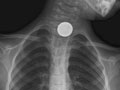

Es posible que su médico recomiende pruebas como una radiografía, una endoscopia o un tránsito esofágico. Estas pruebas pueden ayudar a encontrar el objeto si no se elimina con las heces o si un objeto inhalado no se expulsa al toser. Podría ser necesario usar un detector especial de metales. Puede ayudar a ubicar un objeto de metal, como una moneda, dentro del cuerpo. Luego, su médico puede recomendar un procedimiento para extraer el objeto. O bien, su médico podría alentarlo a que siga revisando sus heces para asegurarse de que el objeto sea eliminado.

¿Se ha tragado una pila tipo botón, un imán o un objeto que contiene mucho plomo, como ciertos juguetes o un plomo de pesca?

¿Se ha tragado una moneda?

¿Se tragó la moneda hace más de 24 horas?

La mayoría de las monedas pasan por el cuerpo sin ningún problema en 24 horas. Si no elimina la moneda en este período de tiempo, lo mejor es hacer un seguimiento con su médico.